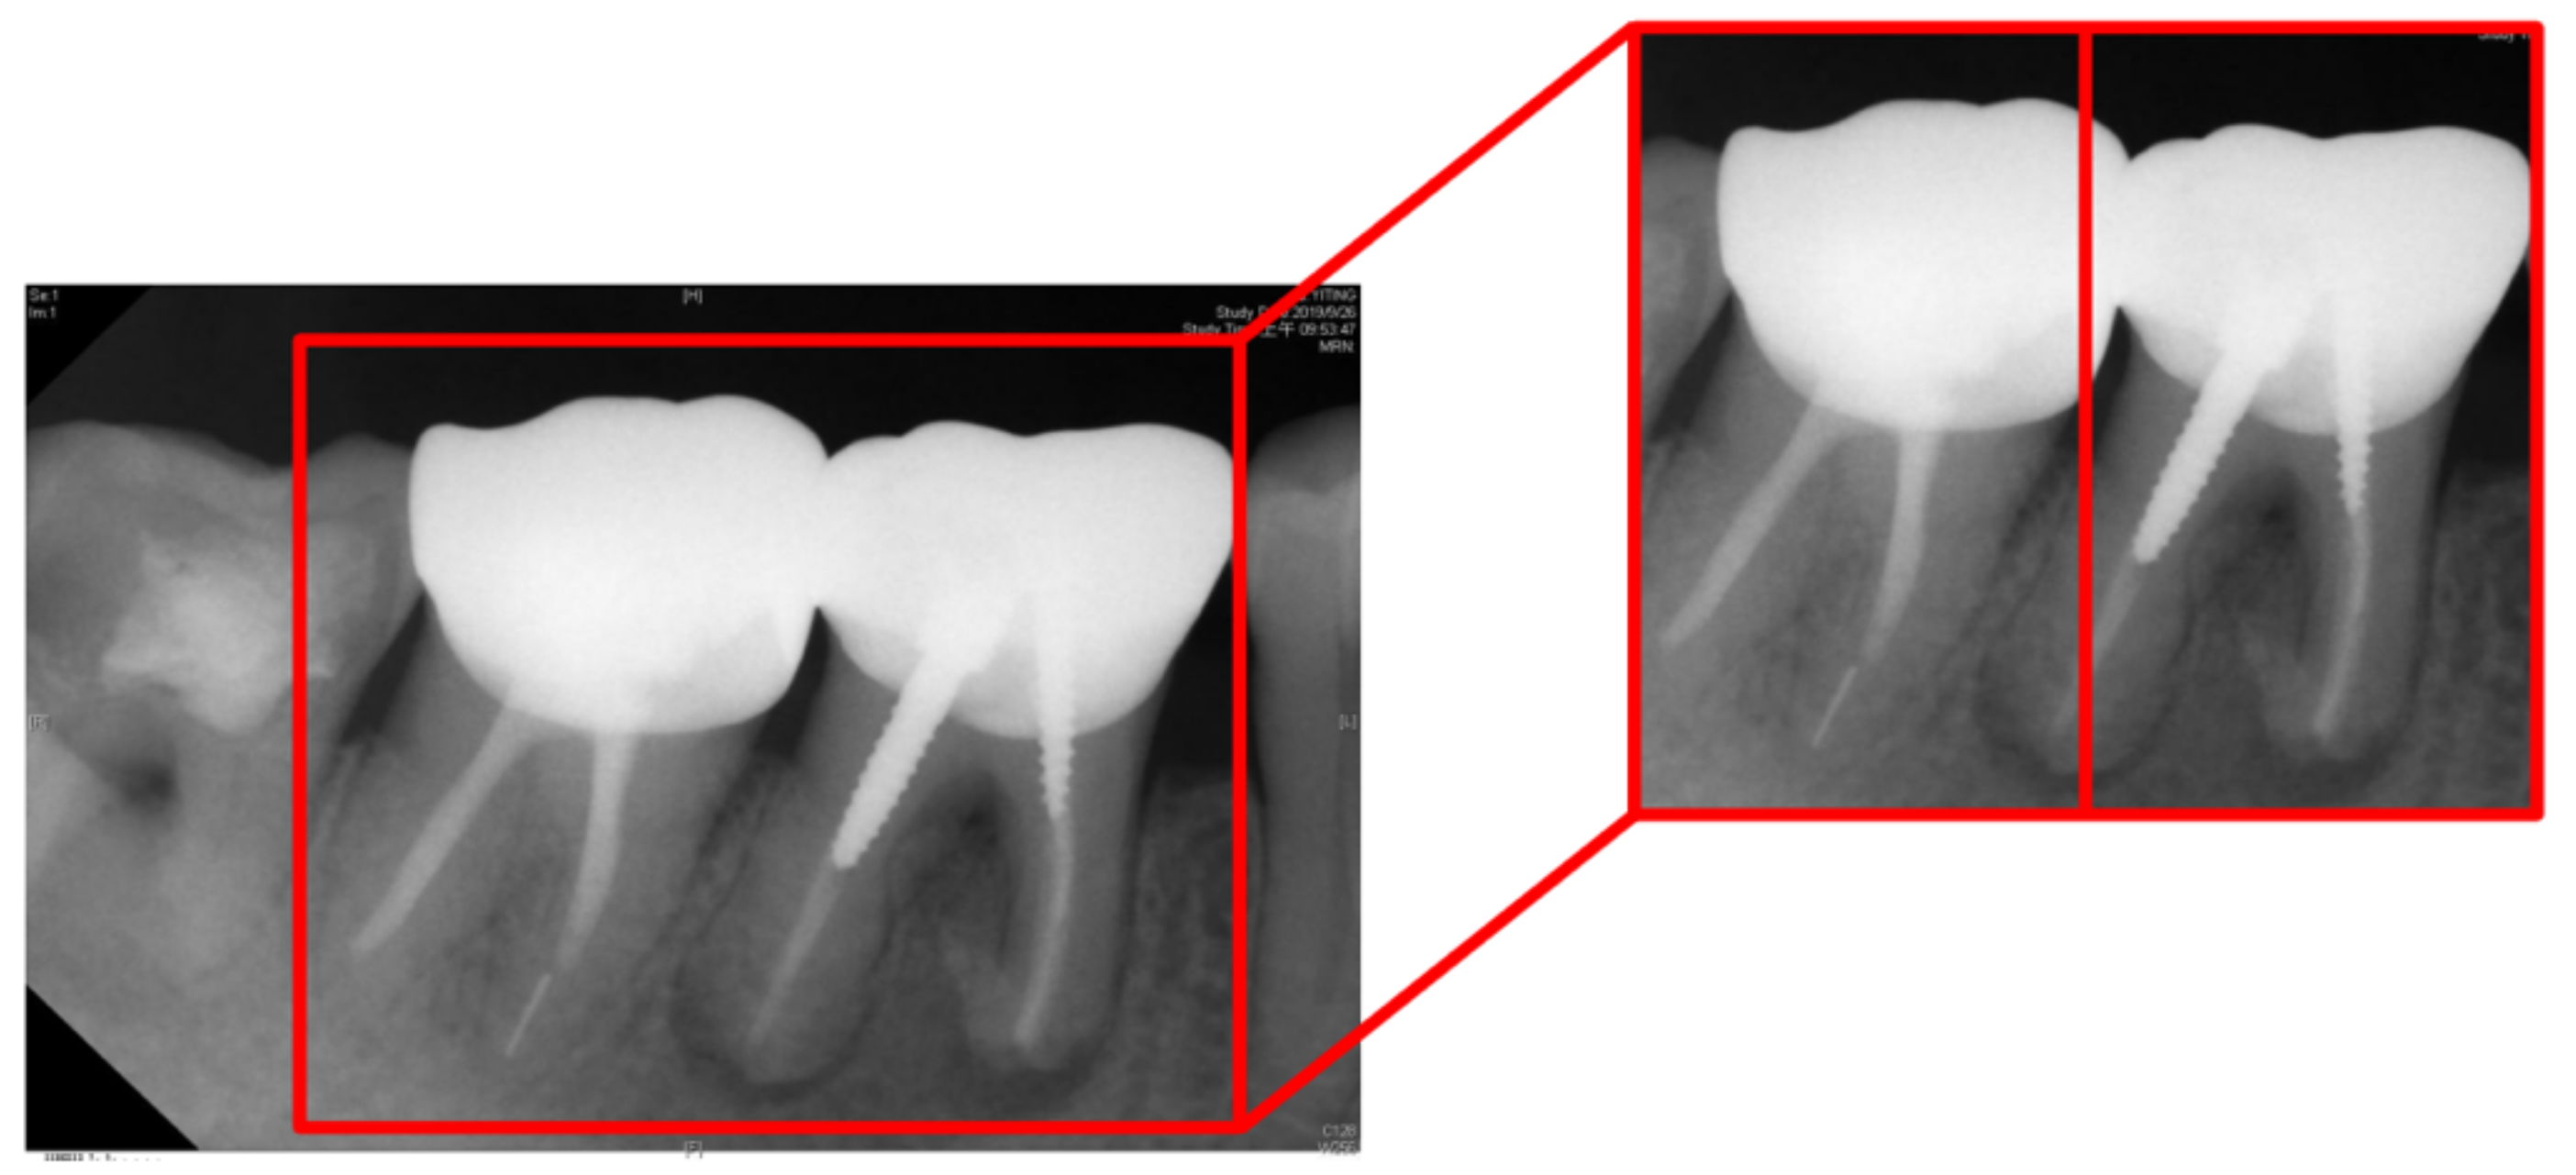

- This study proposes an advanced image enhancement technique for apical lesions. It adds raw grayscale images and Gaussian high-pass filtered images to highlight the possible lesion areas and changes the color of the possible lesion area to green. Experiments show that the accuracy of the model is improved by more than 10% which proves that the proposed method is intuitive and effective.

| Tooth Position in Figure 13 | Left | Right |

|---|---|---|

| Clinical Data | Normal | Lesion |

| This Work Before Enhancement | 90.91% Normal | 94.70% Lesion |

| This Work After Enhancement | 93.93% Normal | 97.35% Lesion |